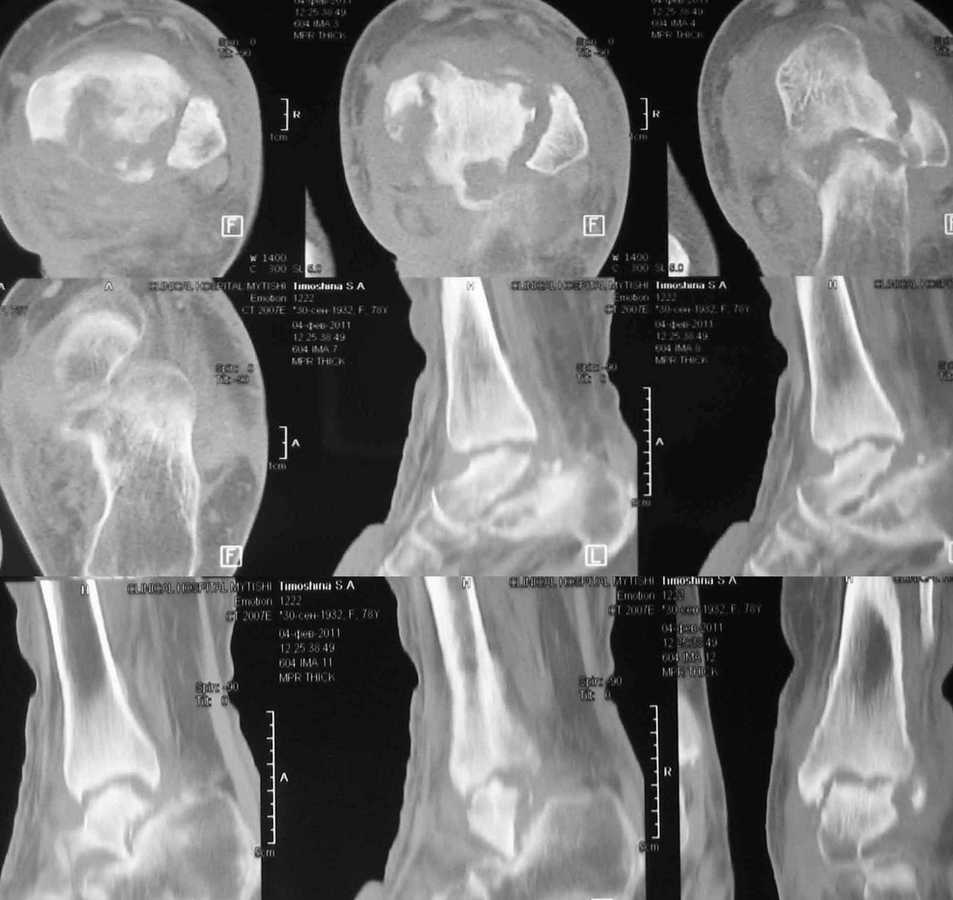

Женщина 78 лет. После инъекции дипроспана (несколько месяцев назад) развился артрит с некрозом тарана

Полгода назад в сустав дважды вводили дипроспан с целью лечения артроза. Спустя некоторое время появился отек, боль и пр. Три месяца назад дугообразным разрезом вскрыли абсцесс по задне-внутренней поверхности голеностпоного сустава. Теперь там свищ со скудным гнойным отделяемым.

КТ и внешний вид на картинках.